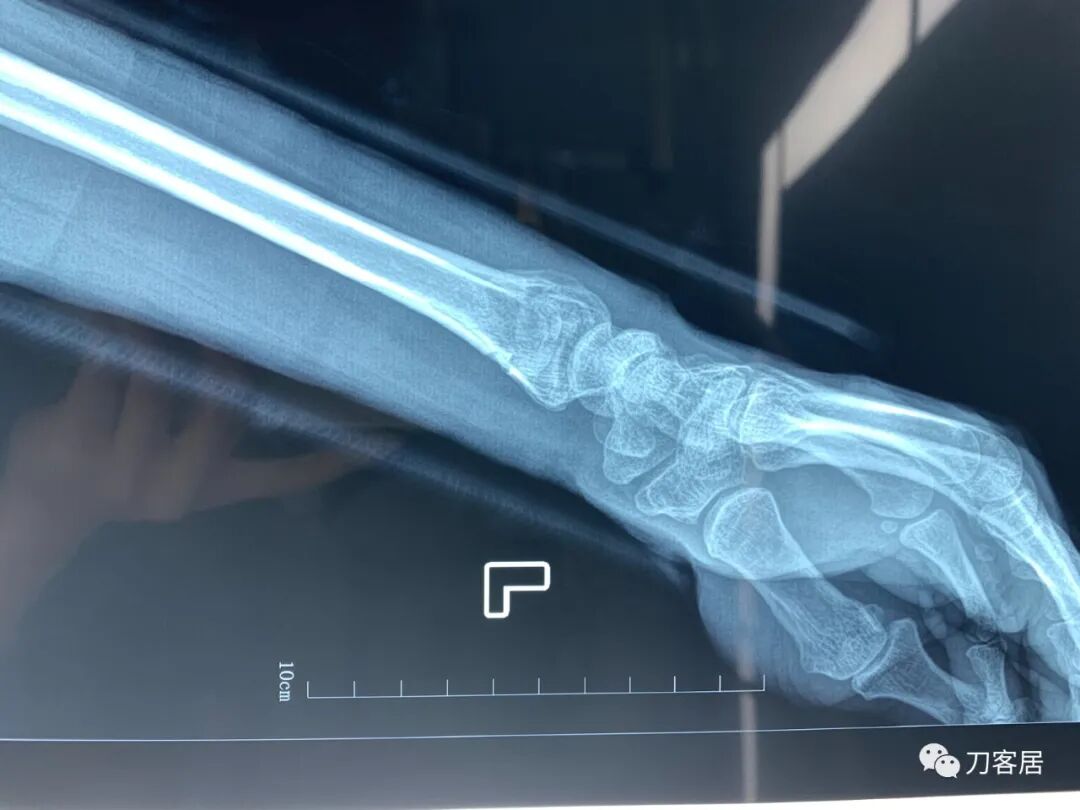

下面是这个6岁孩子,尺桡骨远端双骨折的术前及术后片子和外观照片。

1.  这是一个很简单的6岁儿童无移位的尺桡骨远端骨折。没有皮肤损伤,没有移位,没有骨折碎块儿。

2.  这个骨折处理起来也很简单,单纯的打石膏托或者中医的小夹板,或者正规的包括腕关节和肘关节的管型石膏外固定4周即可治愈该骨折。实在不行,如果这个孩子比较听话,不太调皮的话,用一本书,一个三角巾悬吊固定4周,都可以治愈该骨折。但是给这个患者用外固定架做了手术,而且桡骨远端的几颗克氏针距离骨折线太近,其中一枚克氏针进入到骨折间隙内。从这个术中图片来看,术者的外固定手术技术也有待于进一步的提高。毕竟术者应该还很年轻。从X线片来看,前臂及手的尺侧有不透光影,应该还使用了外固定石膏绷带托,而且我猜测应该是高分子的石膏绷带托,这个是纯属猜测,不一定是对的,不过如何解释前臂尺侧的不透光影呢?如果真是用了石膏绷带外固定的话,那为啥要做手术呢?外固定架术后就不该再用石膏绷带托辅助了。